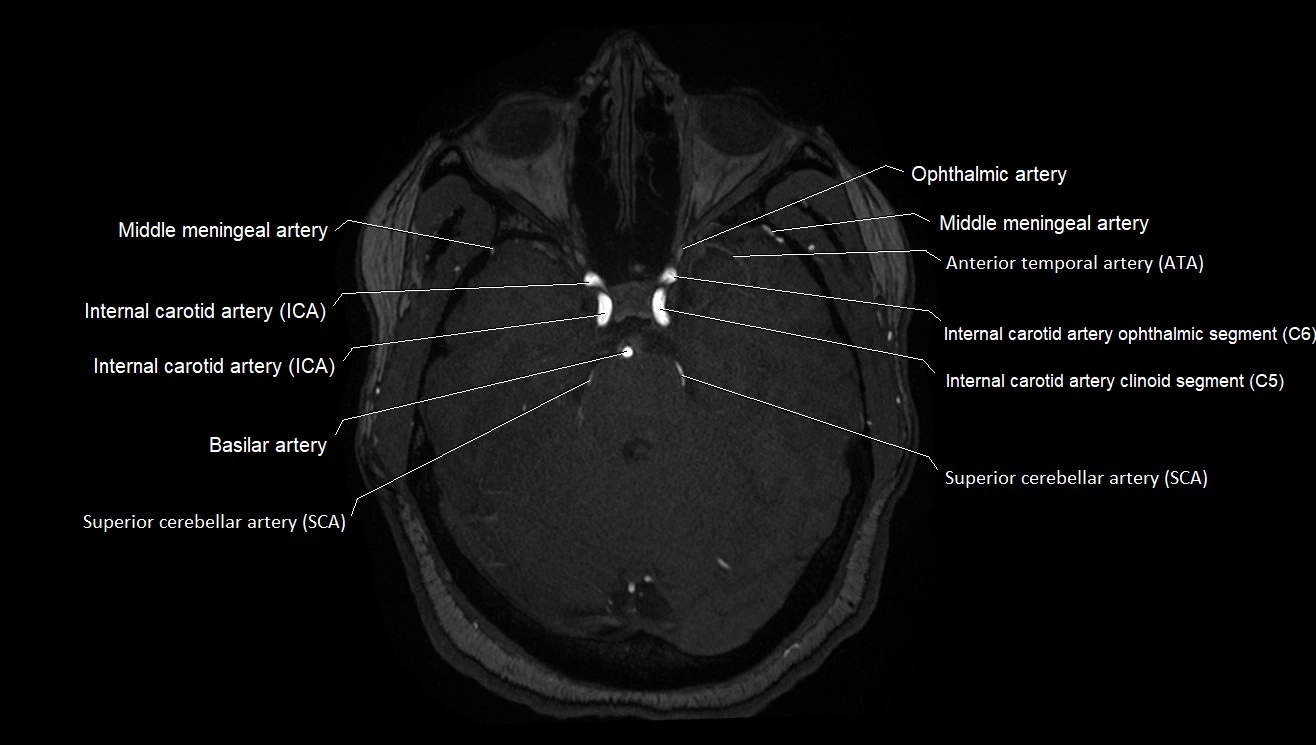

MRA (Magnetic Resonance Angiography):

• Flow-related enhancement makes the AChA appear as a bright, linear vascular signal against suppressed background

• High sensitivity for origin and proximal course; distal branches may be too small to resolve

• Detects stenosis, occlusion, aneurysm, AVM feeders

MRI images

image